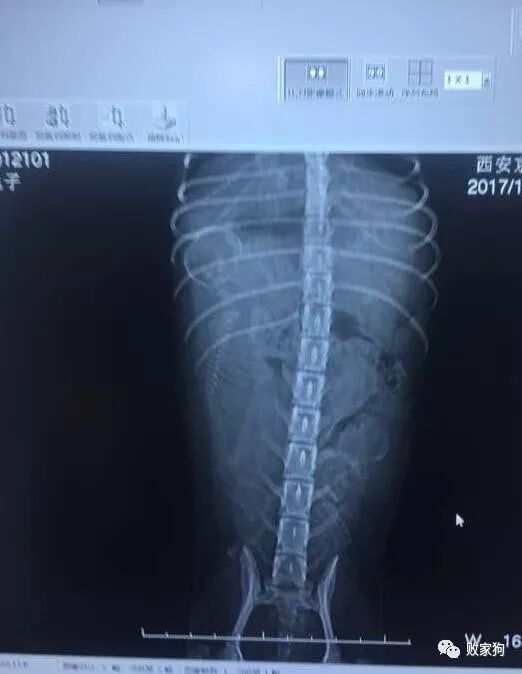

怀孕66天,铲屎官一大早就把可乐送到了宠物医院,经过拍片后,结果让人有点不安。

原来胎儿在可乐体内发育不均衡,有的发育完全,有的还比较小只。为了照顾小只的,可乐的身体本能选择了晚产。